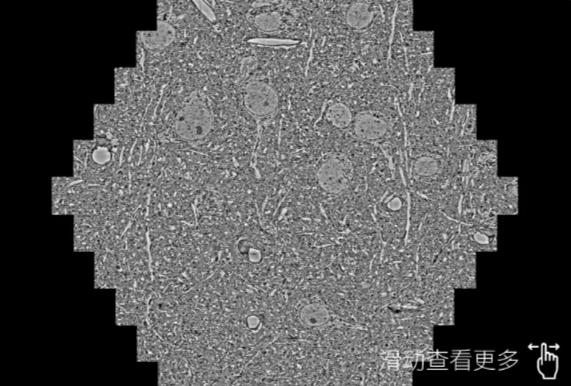

鼠脑切片。左图使用岳阳蔡司岳阳扫描电镜MultiSEM706对165μmx143pm面积区域成像,耗时仅需1.5秒。右图为鼠脑切片中30μm区域放大效果。样品由芝加哥大学B.Kasthuri提供。